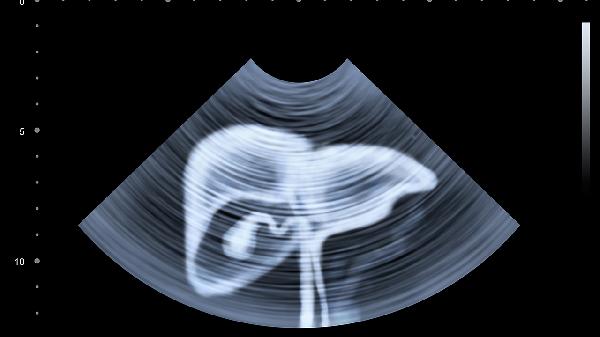

胸腔积液或气胸:肝癌介入手术可能影响胸腔或膈肌功能,导致胸腔积液或气胸。胸腔积液可能压迫肺部,引起胸口痛和呼吸困难;气胸则可能导致胸痛和胸闷。如果疼痛持续或加重,需及时就医,医生可能通过胸腔穿刺或引流排除积液或气体,缓解症状。